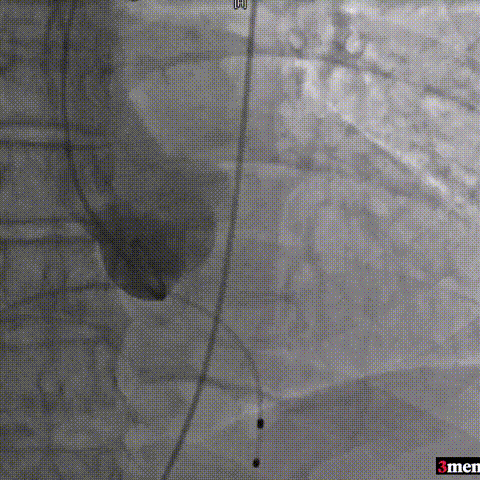

手术过程回顾:

主动脉根部造影

直头导丝跨瓣

球囊预扩

输送器过弓

瓣膜定位

瓣膜释放至工作位

瓣膜脱钩

球囊后扩

术后超声提示患者跨瓣压差即刻显著下降,反流量轻微。术中未出现相关并发症,术后患者心功能持续得到改善,效果良好,圆满取得此次手术成功。